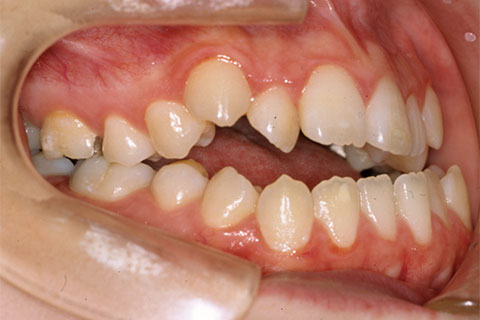

治療前

治療中